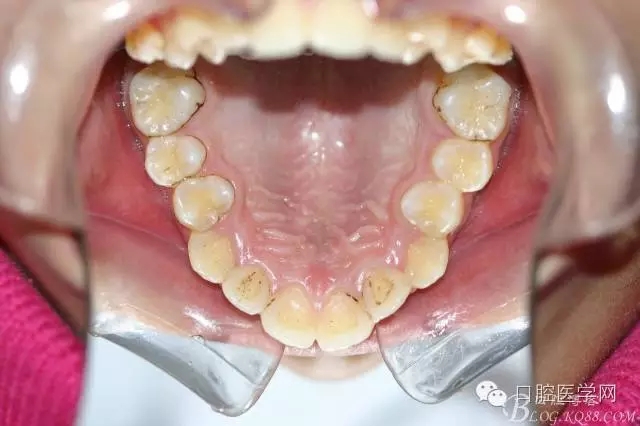

正畸查:替牙合。第一恒磨牙中性合。上牙弓尖圓型下牙弓方圓型。前牙覆合3度覆蓋7.5mm。下前牙咬到上舌側(cè)牙齦。上頜擁擠4.0mm,下頜擁擠

3.0mm。上頜稍前突下頜后縮,上下唇前突,上前牙覆蓋下唇,下唇外翻。面下三分之一過短,頦唇溝明顯,開唇露齒,頦饜窩明顯。顳下頜關(guān)節(jié)開閉口無彈響,無壓痛,開口型開口度正常。

正畸前照片:

正畸后照片: